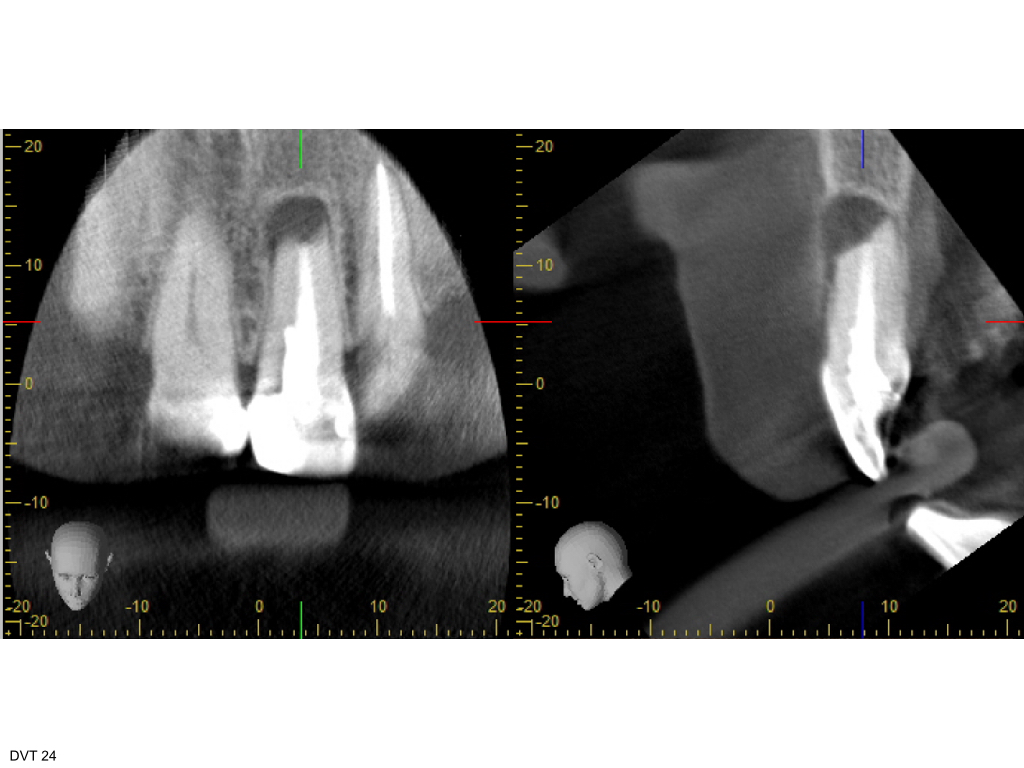

Z.n. WSR